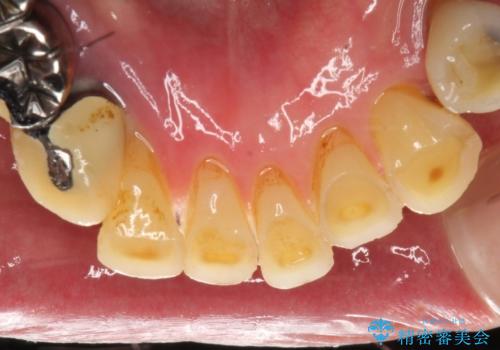

虫歯だらけ、歯周病 崩壊した口腔の再建 フルマウスリコンストラクション

- 歯周外科・インプラント・顕微鏡下根管治療などを含んだ総合的な治療を計画した。

様々な治療手段を高いレベルで同時に併行して行うことが必要でした。

かみ合わせの力が非常に強く、夜間の歯ぎしり・食いしばりもひどかったため、奥歯はメタルオクルーザルの設計でかぶせ物を製作しています。